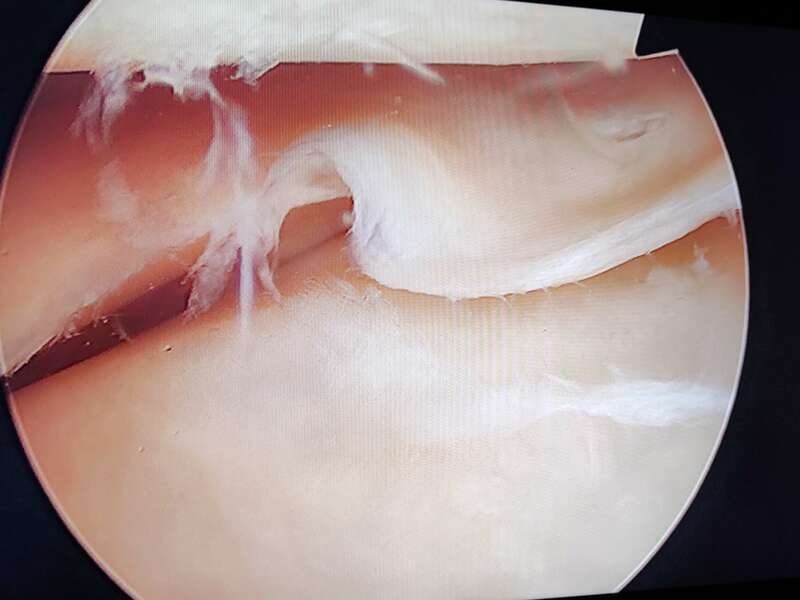

La plupart du temps, les lésions méniscales traumatiques sont traitées chirurgicalement. Deux gestes sont possibles : la réparation méniscale et la méniscectomie. Ces deux interventions sont réalisées au cours d’une arthroscopie et ont des indications spécifiques à chacune.

L’anse de seau méniscale est une fissure verticale qui s’étend de la corne postérieure à la corne antérieure. Cette anse est le plus souvent luxée dans l’échancrure inter-condylienne et provoque des blocages en extension.

Les douleurs sont généralement brutales et intenses avec un gonflement du genou. Le blocage en extension de votre genou correspond à une luxation méniscale dans l’échancrure inter-condylienne (espace situé entre les ligaments croisés et le condyle fémoral). On parle alors de fissure en anse de seau.